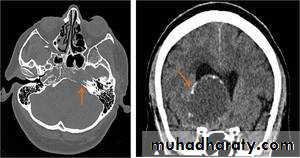

Posterior fosse tumor

Medullo blastoma

Age incidence between 5-15 Y represent about 35-40 %of PFT

Arise from the midline mainly within or from the roof of the 4 TH ventricle fill the fourth ventricle & seeding via the csf so can seen in the distal part of the spinal canal .

CT finding as well circumscribed lesion heterogeneous in density ,have solid & cystic part , with also scattered calcification little surrounded edema , the solid part is enhance

90 % present with obstructive hydrocephalous at the level of the 4Th V. with dilatation of the lateral V. ( body , frontal , temporal & third ventricle )

40 % of child have secondary metastasis at the time of presentation